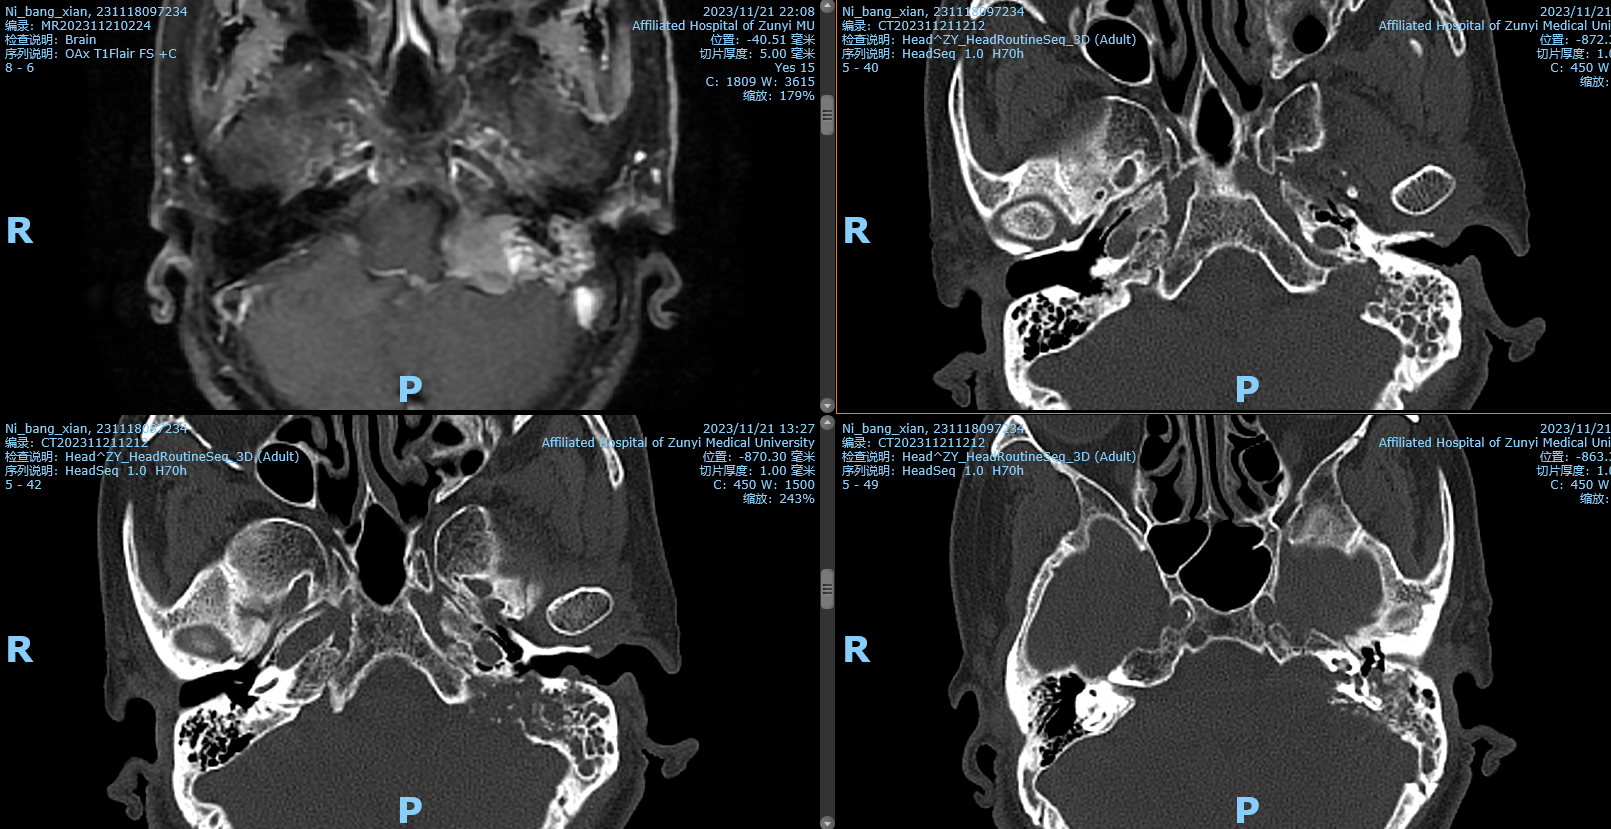

56岁女患,因“口角右歪伴左眼闭合不全18个月”入院。查体:生命体征平稳,双侧瞳孔正常,光反射灵敏,左眼闭合不全,左侧额纹、鼻唇沟消失,口角右侧歪斜。House-Brackmann(H-B)分级 :IV级四肢肌力5级,肌张力无异常,生理反射存在,病理反射未引出。颅脑MRl:1左侧桥小脑角区占位,考虑听神经鞘瘤伴囊祥变。

阅片后考虑为左侧内淋巴囊肿瘤,侵犯岩骨,破坏面听神经,手术方案选择:左侧乙状窦前入路,窦前入路切除CPA区肿瘤,同时做岩骨次全切,术中发现面神经破坏,截取左侧耳大神经作为桥接神经,行左面-舌下神经端侧吻合,关颅后发现左侧外耳道与颅内相通,脑脊液缓慢流出,又在神经内镜下行外耳道缝扎术,术后2周出院,无脑脊液耳漏、鼻漏。术后病理后免疫组化证实为内淋巴囊肿瘤,ki-67达20%。

影像学检查:ELST起源于内淋巴囊或内淋巴管,因此早期以岩锥后缘后半规管后方内淋巴囊部位为中心生长,逐渐侵蚀颞骨其他部位。

术式的选择应根据术前听力及肿瘤临床分级决定。Ⅰ级,肿瘤局限于迷路后区域,通常为轻至中度听力下降,为保留这类患者的残余听力,选择迷路后径路+岩骨后部切除术。Ⅱ级,肿瘤主要朝前侵犯但仍局限于颞骨内,此时迷路或内听道受累,因此患者听力呈重度下降,为完全切除肿瘤,通常选择经迷路径路颞骨次全切除术。Ⅲ级,肿瘤侵犯颞骨外结构,Ⅲa级累及颈静脉孔相关结构,推荐采用颞下窝径路切除肿瘤;Ⅲb级累及颅内,通常采用颞下窝入路结合乙状窦后入路或颅中窝入路。若肿瘤累及颈静脉球,出血风险大,术中我们可在通过闭塞乙状窦和结扎颈内静脉后,使用乙状窦隧道填塞岩下窦技术控制岩下窦出血,同时还能避免后组脑神经损伤,进而切除颈静脉球外侧壁及肿瘤。如肿瘤向外累及外耳道,同时颅内肿瘤直径>2 cm,此时可二期切除颅内肿瘤,避免脑脊液漏的发生。对于面神经未受累及的早期肿瘤患者,术中应注意避免损伤面神经及其骨管;对于面神经受累及的患者,应切除受累面神经,并同期行面神经-耳大神经吻合术或面神经-舌下神经吻合术。采用颞下窝径路时,为了更好地暴露肿瘤,可将面神经部分前移位或使用面神经骨桥技术。累及颅内的患者,可根据肿瘤大小,同期或分期切除颅内肿瘤。为预防术后脑脊液漏和颅内感染,术中可用人工脑膜、肌肉及脂肪修补脑脊液漏,用肌肉及骨蜡封闭咽鼓管,将蒂在后方的肌骨膜瓣同前方腮腺后缘缝合,并封闭外耳道。